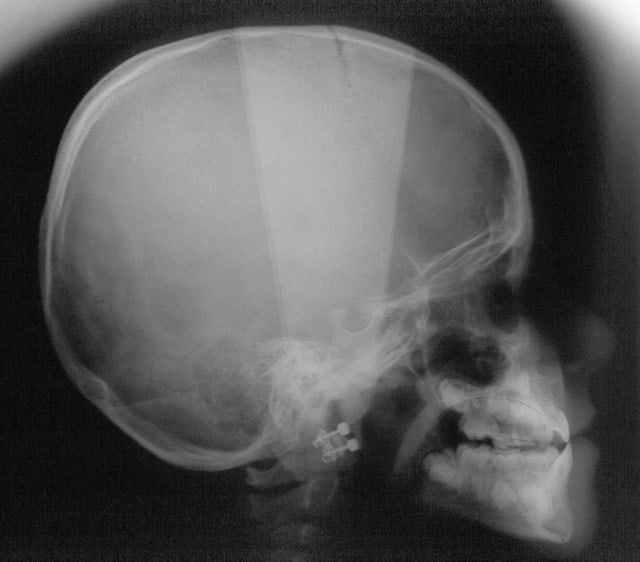

chakour

22/05/2008 à 00h10

début 2008,quadhélix en 0.28,pour vestibuler la 2,ce qui est fait

Tele2002 qhiepn - Eugenol

Tele2007 b6yul0 - Eugenol